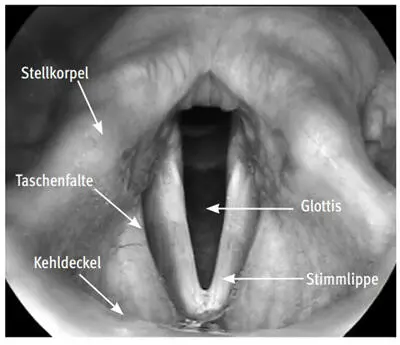

Abb. I.57: Blick von oben in den Kehlkopf

Teilweise Verschlüsse der Stimmlippen können auch regelhaft bei Bläsern während des Spielens beobachtet werden. Eine Beschreibung der bei den verschiedenen Blasinstrumenten im Kehlkopf ablaufenden Vorgänge findet sich in Kap. I.1.3, S. 49 ff.